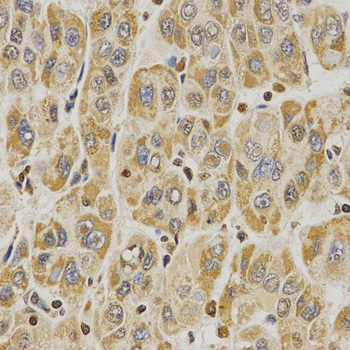

Immunohistochemistry of paraffin-embedded human liver cancer tissue using H3R8me2s antibody at dilution of 1:200 (x400 lens).